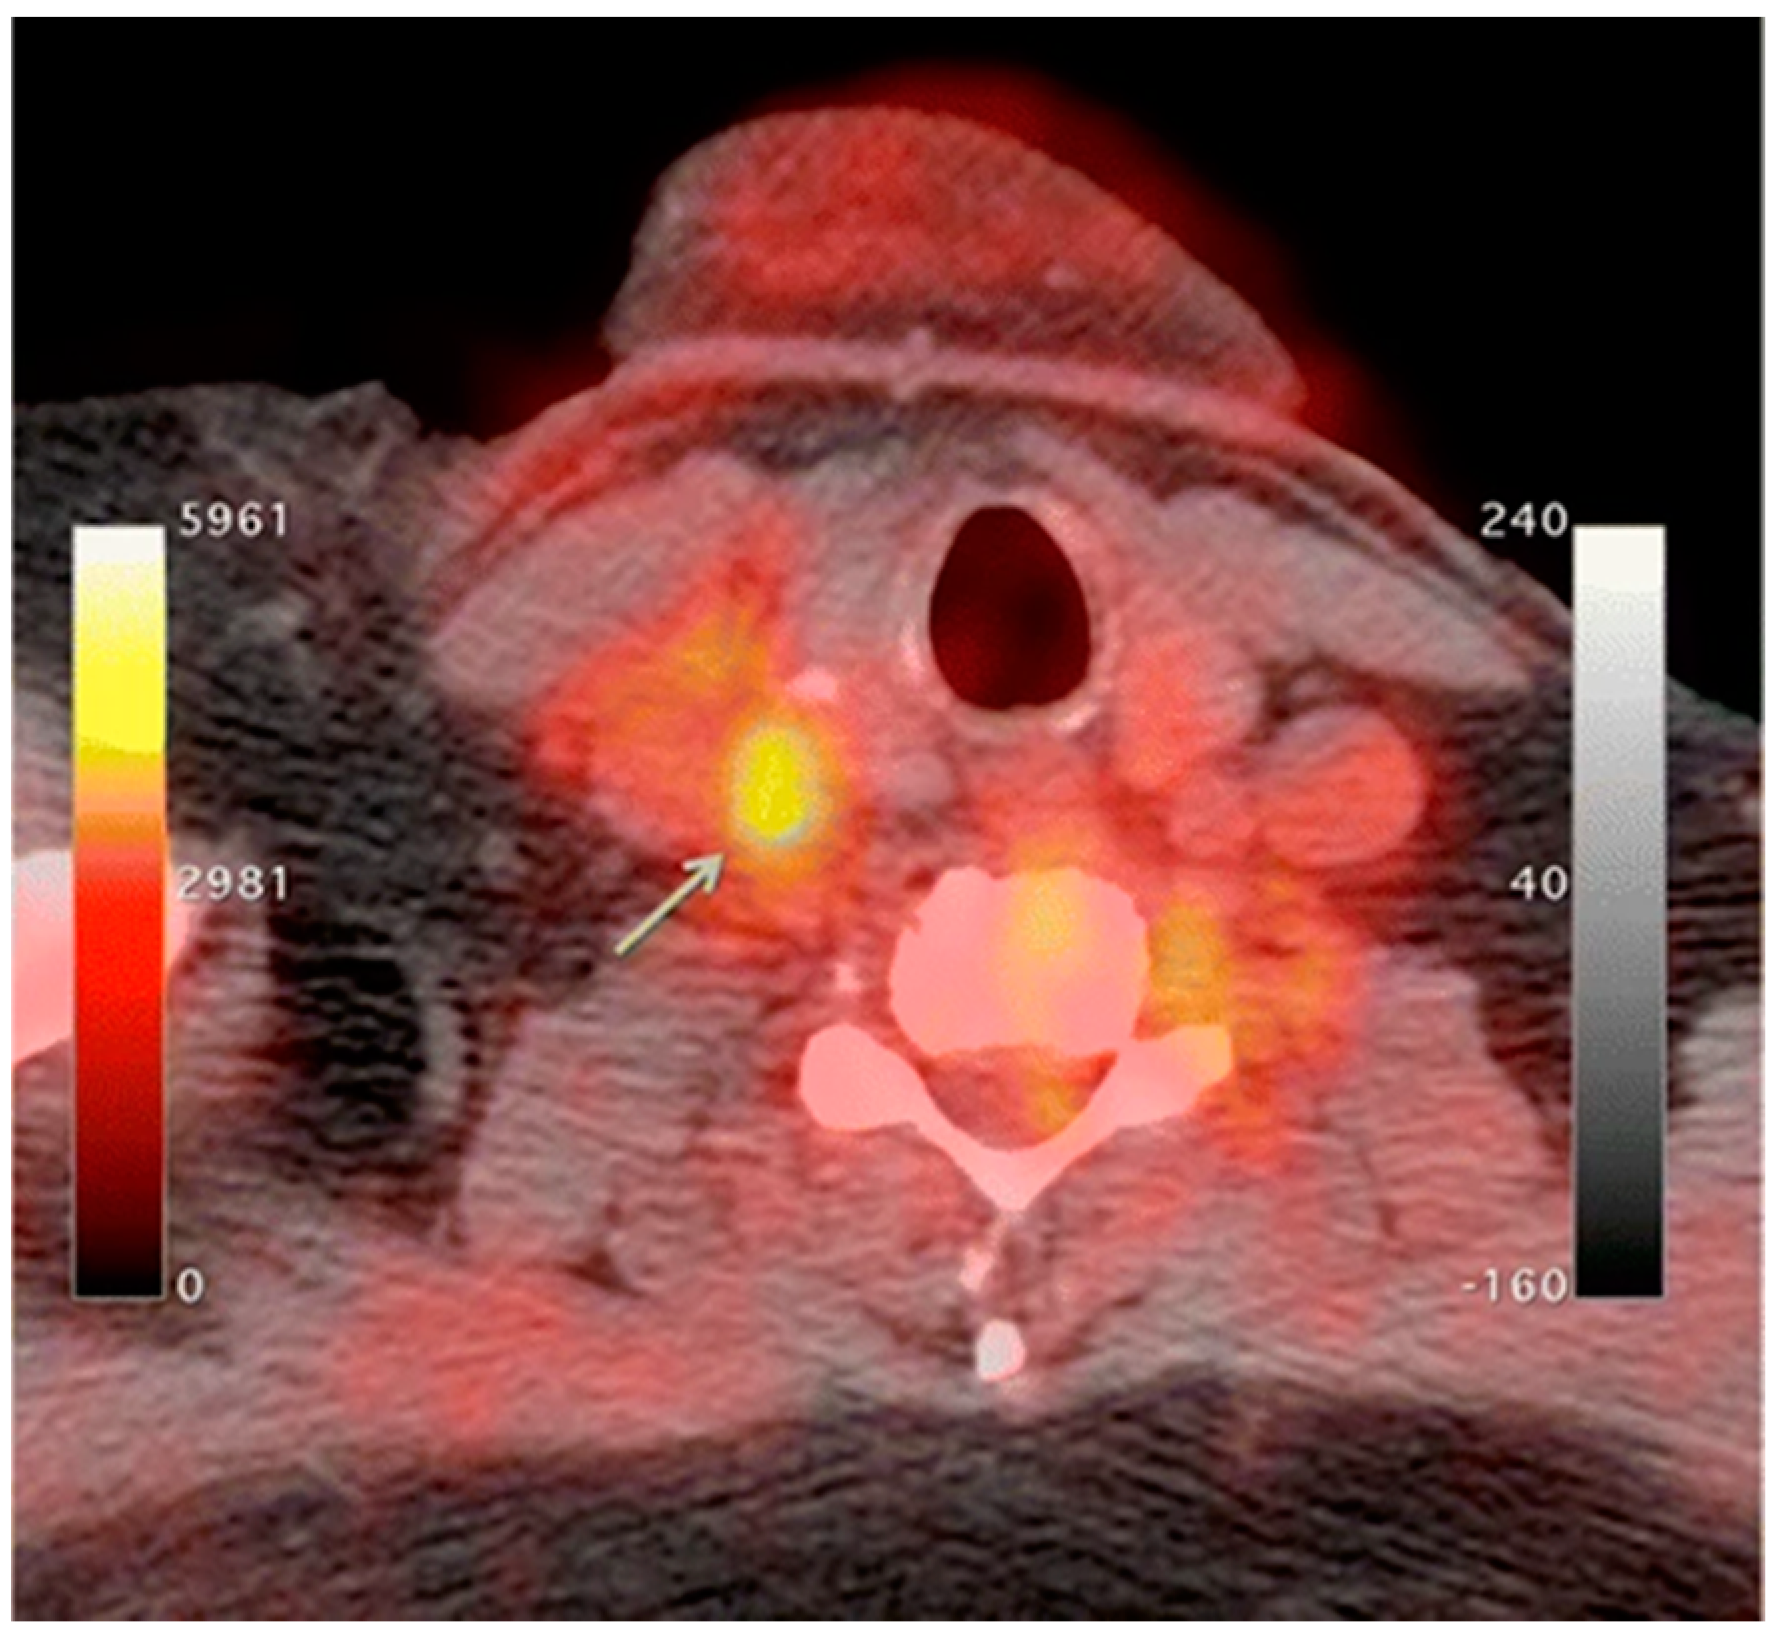

- Catalano, O.A.; Wu, V.; Mahmood, U.; Signore, A.; Vangel, M.; Soricelli, A.; Salvatore, M.; Gervais, D.; Rosen, B.R. Diagnostic Performance of PET/MR in the Evaluation of Active Inflammation in Crohn Disease. Am. J. Nucl. Med. Mol. Imaging 2018, 8, 62–69. [Google Scholar]

- Le Fur, M.; Zhou, I.Y.; Catalano, O.; Caravan, P. Toward Molecular Imaging of Intestinal Pathology. Inflamm. Bowel Dis. 2020, 26, 1470–1484. [Google Scholar] [CrossRef]